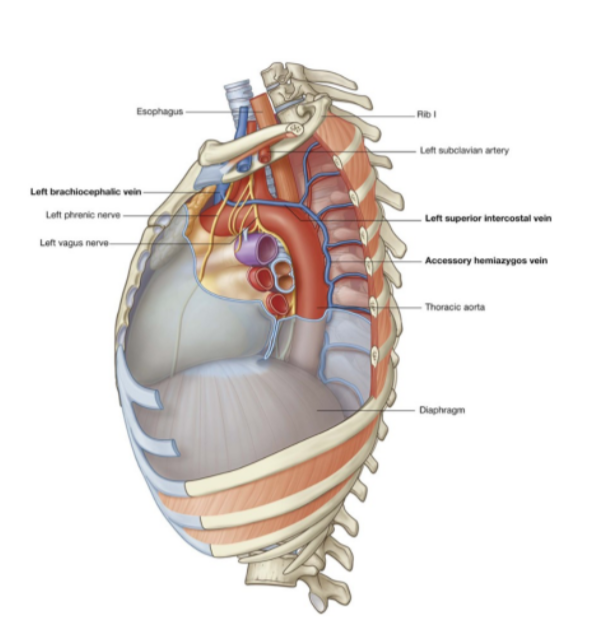

Left superior intercostal vein

Receives the second, third, & sometimes 4th posterior intercostal veins, usually the left bronchial veins, & sometimes the left pericardiacophrenic vein

Passes over the left side of the aortic arch, lateral to the left vagus nerve & medial to the left phrenic nerve, before entering the left brachiocephalic vein

Inferiorly may connect with the accessory hemiazygos vein (superior hemiazygos vein)

Right & left vagus nerves of superior mediastinum

Left vagus nerve —

Enters mediastinum between left brachiocephalic vein & left common carotid artery

Passes posteriorly to the root of the left lung

At the level in which it crosses to the lateral side of the arch of the aorta there is the origin of the laryngeal nerve